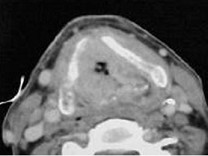

男,55歲,聲嘶6年,有長期吸煙史。檢查:無呼吸困難。喉鏡檢查:聲帶慢性充血,可見右側(cè)聲帶可見菜花樣新生物,右側(cè)聲帶活動(dòng)固定,喉部CT檢查如下圖: